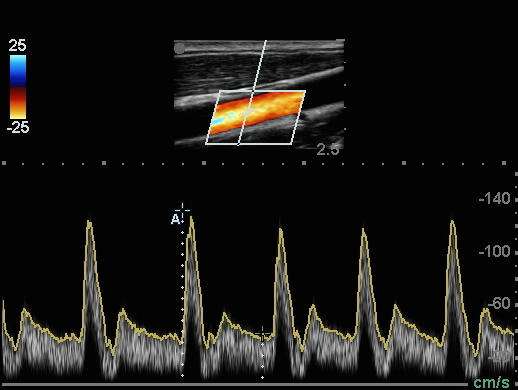

共通の頸動脈の内頚動脈 (CCA) ドップラー測定画像